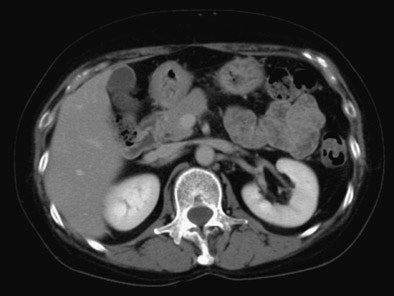

![]() |

| Above, 5-second delay (renal arterial phase) 73-year-old female patient. All images courtesy of Dr. Hironori Nishibori and Dr. Masa Kanematsu. |